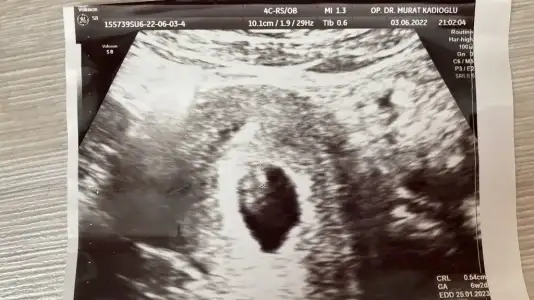

Mrb benimkine bakabilirmisiniz 10+1 karından

Eklentiler

• 20220613_135400.webp

20220613_135400.webp

28,8 KB · Görüntüleme: 56